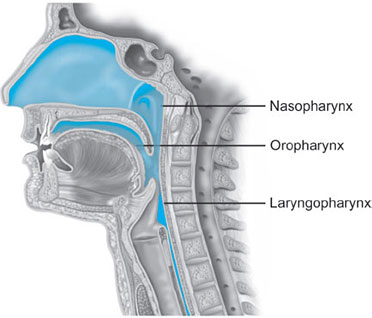

Parts (Fig. 1)

- Nasopharynx: Extends from skull base to soft palate at caudal aspect of C1

- Oropharynx: Extension of nasopharynx to caudal aspect of C3; also involves anterior 1/3 to posterior 2/3rd of tongue

- Layngopharynx (hypopharynx): Merges with esophagus at C6, where the cricopharyngeus encircles the esophagus to form its upper sphincter (similar function of Sellick's maneuver in anesthetized patients).